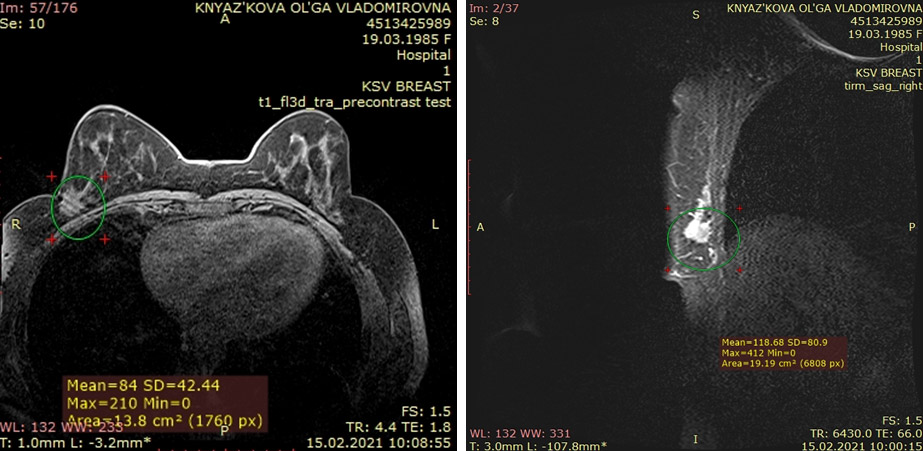

Опыт из практики: люминальный B, HER2 отрицательный тип, рак правой молочной железы T2N0M0 G2

Диагноз: люминальный B, HER2 отрицательный тип, рак правой молочной железы T2N0M0 G2. 4 курса неоадьювантной химиотерапии по схеме AC. Стабилизация.

Операция: радикальная секторальная резекция правой молочной железы с подмышечной лимфадиссекцией.